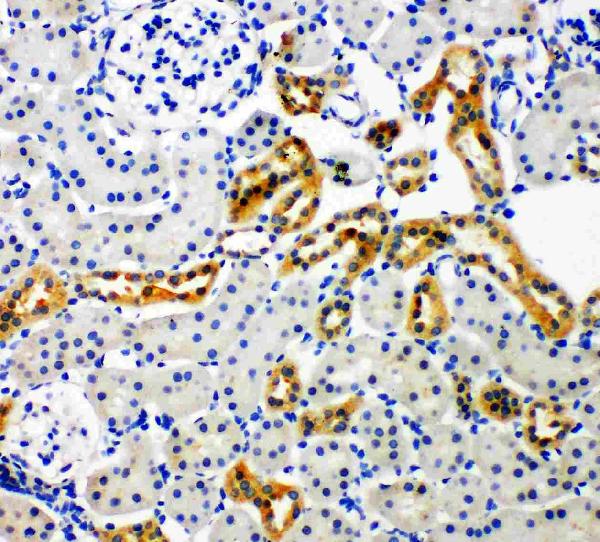

- Scientific DescriptionBoster Bio Anti-NADPH oxidase 4/NOX4 Antibody catalog # PA1929. Tested in Flow Cytometry, IHC, IHC-F, ICC, WB applications. This antibody reacts with Human, Mouse, Rat. The brand Picoband indicates this is a premium antibody that guarantees superior quality, high affinity, and strong signals with minimal background in Western blot applications. Only our best-performing antibodies are designated as Picoband, ensuring unmatched performance.

ApplicationsFlow Cytometry, Western Blot, ImmunoCytoChemistry, ImmunoHistoChemistry, ImmunoHistoChemistry Frozen

- ApplicationsFlow Cytometry, Western Blot, ImmunoCytoChemistry, ImmunoHistoChemistry, ImmunoHistoChemistry Frozen